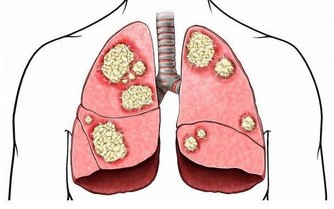

3、抗結核藥物

吡嗪酰胺和乙胺丁醇是熟知的抗結核藥,你如果看看藥物的使用說明書,裡面清楚的寫著,可能會導致尿酸增高。但是,很有意思的是,同樣作為抗結核藥物的利福平卻可以抑制尿酸的吸收,如果將這三種抗結核物質一起服用,並不會引起尿酸的過度升高。